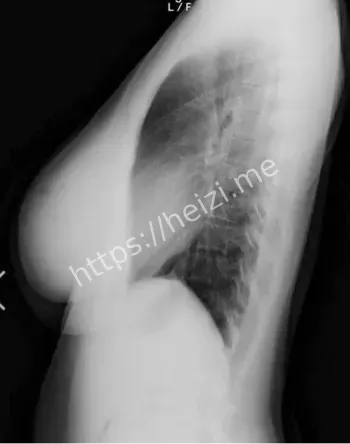

哎呀,这天木纯的八卦又炸锅了,最近网上疯传她的X光照片,说是巨乳假体曝光,粉丝们一看都傻眼了。这位1995年生的小纯,本来就是以童颜巨乳出名的AV女优,身高才148公分,三围99I-57-84,那对G杯胸器大得像漫画里蹦出来的,二次元天乳的称号不是白叫的。报道说X光片显示胸部结构不自然,有人直呼卧槽太夸张了,怀疑是假体植入啥的。话说回来,这事儿一出,黑子网用户们就热闹了,各种分析帖刷屏,说这不光是身材秘密,还牵扯到AV圈的整形风潮。

啧啧,天木纯的二次元天乳这回可出大事儿了,X光照片流出后,身材秘密被扒得底朝天。网传她那99公分的胸围太不科学了,童颜小身板配巨乳,粉丝们以前直呼福利,现在却开始纠结假体问题。报道分析说,X光显示植入物痕迹明显,可能是硅胶假体啥的,这在AV女优圈挺常见,追求完美身材嘛。可天木纯本人没回应,粉丝热议分成两派,一派说天生丽质,一派说整形无罪。哎,这身材秘密一曝光,二次元天乳的魅力打折了?大家说,这事儿提醒女优们,真实比假象重要,粉丝也得学会欣赏内在。

哈哈,这天木纯巨乳假体争议可真叫人看热闹不嫌事儿大,X光曝光后,粉丝热议焦点全在她身上了。AV女优圈里,她以童颜巨乳闻名,二次元天乳粉丝无数,可这回X光片一出,直指假体植入,网友们炸了锅,有人说卧槽确实好大太假了,有人辩护说天生就这样。报道说,事件源于某论坛泄露的照片,专业人士分析胸部密度异常,疑似假体手术痕迹。这粉丝热议不光是八卦,还涉及对女优形象的认知,大家说AV界整形常态,但曝光后就尴尬了,得保护隐私啊。

哇塞,天木纯X光照片流出这事儿,社会影响可不小,AV女优圈的假体风波又被推上风口。报道说,这照片疑似医疗记录泄露,巨乳结构一览无余,二次元天乳的完美形象瞬间崩塌,粉丝们从惊呼福利到热议争议。童颜巨乳是她的卖点,可假体曝光后,大家开始讨论AV产业的身材压力,女优们为工作整形在所不惜,这社会影响深远啊。话说,这事件还牵扯隐私权,X光本是私密,怎么就流出了?得加强保护,不然谁敢安心工作。